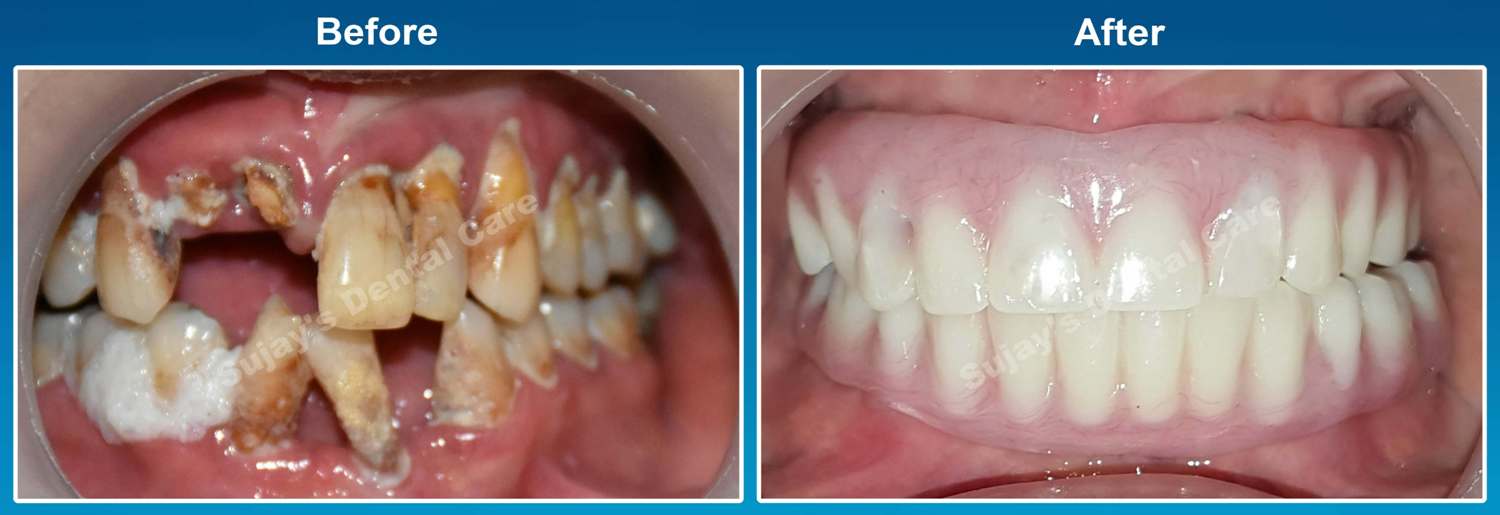

Before & After